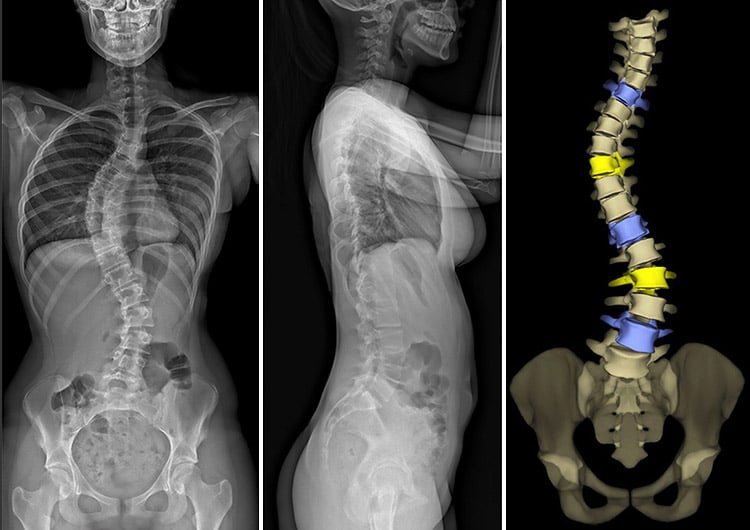

EOS images of a patient with scoliosis: 2D anteroposterior (frontal) and lateral (outer side) X-ray views, and 3D anteroposterior rendering of the spine and pelvis.

EOS imaging is a low-dose, weight-bearing X-ray technology. It can simultaneously take full-body, frontal and lateral (side view) images of the skeletal system of a patient in a standing or sitting position, using significantly less radiation than traditional X-rays or CT scans.

Using EOS, two dimensional (2D) and three-dimensional (3D) orthopedic images can be produced to assist doctors with the diagnosis and treatment of medical conditions of the spine, hips and knees.